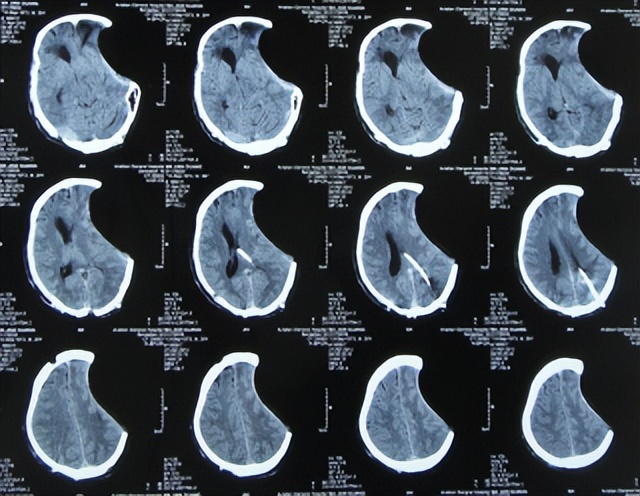

入院当天进行了脑室外引流术。术后次日查头颅CT示脑室缩小,脑膨隆变基本正常( 图-13 )。

图-13: 2013年3月6日头颅CT

脑脊液各项指标化验正常后于2013年3月26日(治疗21天),进行了左侧脑室-腹腔分流术( 图-14 )。

图-14: 2013年3月26日头颅CT

2013年4月7日(治疗33天)出院,出院时:脑积水颅内感染已治好,意识由入院时昏迷变意识模糊,自动睁眼,遵嘱活动差;左额颞顶区原去骨瓣手术切口破溃已经愈合,大小便变正常( 图-15 );头颅CT示仍遗留颅骨缺损( 图-16 )。

图-16: 2013年4月7日出院时头颅CT